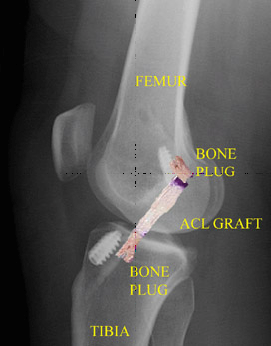

Introducción de un injerto de tendón rotuliano en el túnel tibial de la rodilla.

La radiografía posoperatoria después de la reconstrucción del LCA con el tendón rotuliano (con una imagen superpuesta del injerto) muestra la posición del injerto y la fijación de los tapones óseos con tornillos interferenciales metálicos.

En la técnica de reconstrucción del LCA más frecuente, el cirujano perfora túneles en la tibia y el fémur para poder colocar el injerto del LCA con un posicionamiento lo más anatómicamente correcto posible. Una vez colocado el injerto en la rodilla, se mantiene en tensión y se fija en su lugar con tornillos, botones u otro dispositivo. Por lo general, estos dispositivos no se extraen después de la cirugía.